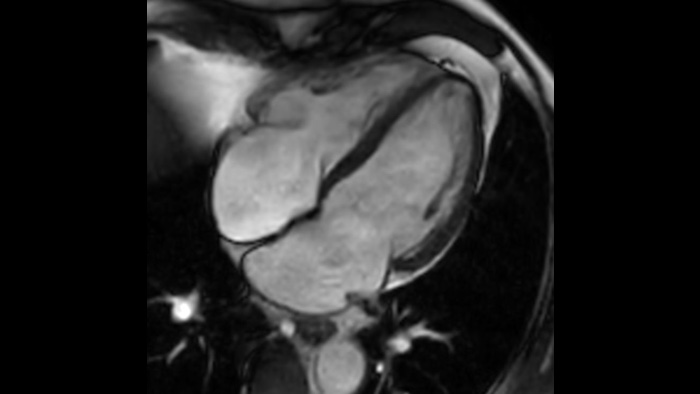

Speed & Comfort Provide up to 40% reduction in breath holds, with virtually equal image quality4.

The Ingenia Ambition 1.5 Tesla magnet is the next generation of MR technology. It brings together the most important aspects of having a successful MR system.

This innovative solution offers many clinical, operational and financial benefits.